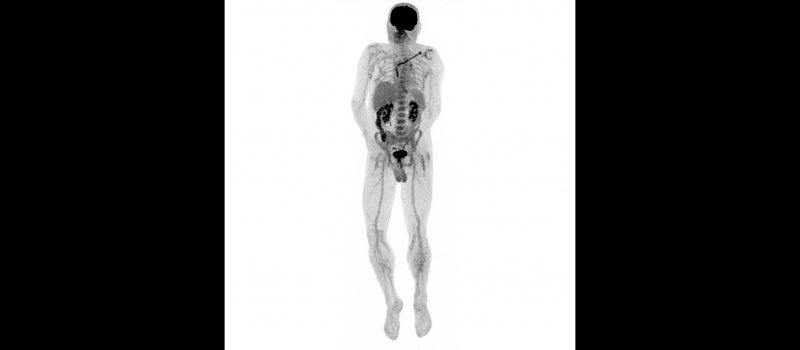

Kontrolní TEE na našem pracovišti potvrdila vlající vegetace v pravostranných srdečních oddílech – největší o velikosti 25×9 mm, menší přisedlý útvar s rozměrem 7×9 mm. Provedené PET/CT bylo v korelaci se suspektními zánětlivými změnami téměř v celé délce elektrod. V rámci multidisciplinárního týmu bylo vzhledem k velikosti vegetací a rizikovým faktorům rozhodnuto o kardiochirurgické extrakci stimulačního sysému. Transvenózní extrakce představovala větší riziko s nejasným výsledkem - možné embolizace do plic, mechanické komplikace s ohledem na stáří elektrod a známý uzávěr levé v. subclavia. Předoperační přípravu zkomplikovala hluboká žilní trombóza vlevo, která vedla k odkladu výkonu. Začátkem srpna pacient podstoupil kardiochirurgickou extrakci celého systému. Vlastní výkon i pooperační průběh byl bez komplikací a pacient byl přeložen zpět do spádové nemocnice k pokračování antibiotické léčby.